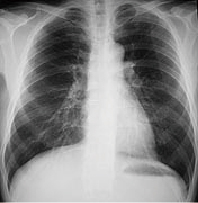

X線撮影検査

一般的にレントゲン検査と呼ばれている検査です。

X線を用いて体内の骨や組織、器官などの構造を平面的に画像化する検査です。

撮影後、FCRというシステムを使用して画像処理されます。